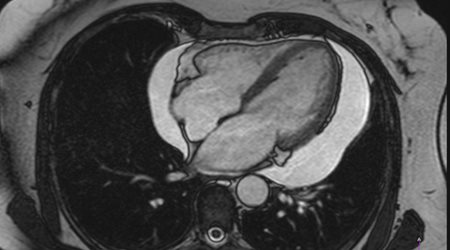

التهاب و عفونت قلب

پریکاردیت 🔗

Pericarditis

میوکاردیت 🔗

Myocarditis

اندوکاردیت 🔗

Endocarditis

کرونا ویروس 🔗

Corona Virus

روماتیسم قلبی (تب حاد روماتیسمی)

توضیح در مورد تب روماتیسمی حاد و عوارض طولانی مدّت آن بر قلب